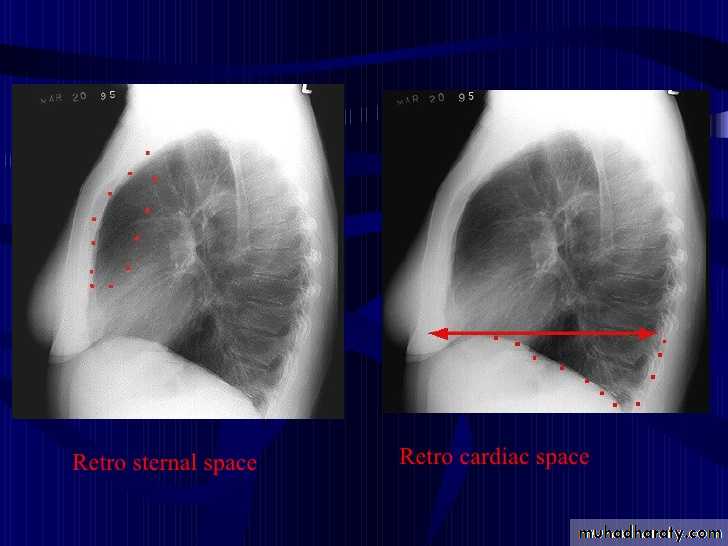

Chest imagingHilar structuresThe hila (lung roots) are complicated structures mainly consisting of the major bronchi and the pulmonary veins and arteries. These structures pass through the narrow hila on each side and then branch as they widen out into the lungs. The hila are not symmetrical but contain the same basic structures on each side.

The left hilum is often higher than the right

Both hila should be of similar size and density. If either hilum is bigger and more dense, this is a good indication that there is an abnormality.